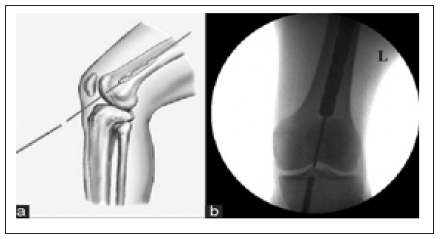

The incidence of distal femur fractures is around 37/100,000 patients per year [1]. Characteristically, two separate mechanisms of injury cause distal femur fractures. In the elder population with osteoporotic bone and susceptible soft tissue envelope, distal femoral fractures occur predominately after low energy trauma, e.g., falls and sprain injuries complicated by a high rate of comorbidity (60% female, older than 60 years). In young patients (60% male, younger than 40 years), high energy trauma causes complex injury with comminuted and open fracture pattern. Approx. 30% of patients with distal femur fractures are poly traumatized. 40% had soft tissue injuries, 10% had ligamentous lesions, 8% had meniscal lesions, 10% had dissected cartilage fragments and 15% had patella fractures and 38% of supracondylar/intercondylar distal femoral fractures have a coronal plane fracture [2-6]. Intramedullary femoral nailing has classically been performed using antegrade entry from piriformis fossa and has produced excellent results. Winquist et al had 99.1% union rate with postoperative knee ROM averaging 130degree and 0.9% infection rate [7]. Since antegrade nail has been so successful there has been resistance in surgeons to accept retrograde nailing as an alternative as shown in Figure 1 & 2; [8].

Figure 2: Postoperative radiographs of a distal third femoral shaft fracture treated with a retrograde interlocking nailing.